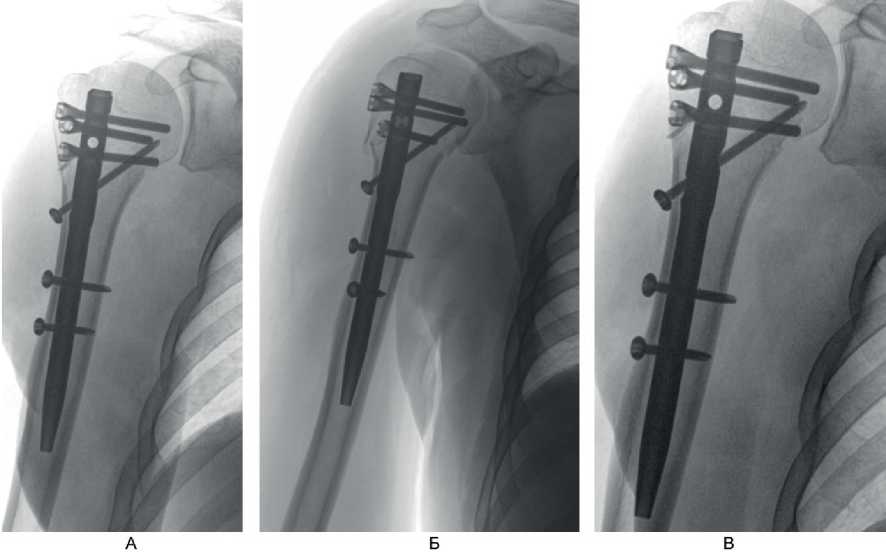

Перелом по классификации АО – С3.1. На 2-е сутки после поступления выполнено оперативное вмешательство – БИОС хирургической шейки правой плечевой кости. Рентгенография на 1-е сутки после операции представлена на рис. 9А, Б, контрольная рентгенография плечевого сустава через 6 мес после операции – на рис. 9В. Функциональный результат после операции – на рис. 10.

Рис. 9. Больной А., 50 лет. А, Б – рентгенография на 1-е сутки после операции; В – через 6 мес после операции